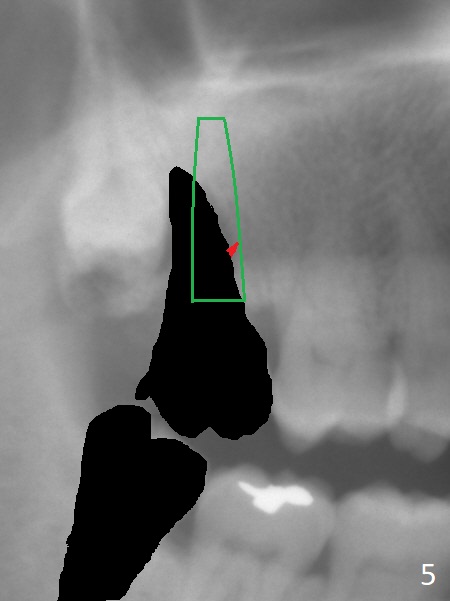

A 67-year-old man has pain associated with the tooth #2 with distal deep pockets (Fig.1), consistent with root fracture. The abnormal force may arise from the mesioangular lower 3rd molar (Fig.2 arrow). To avoid damage to the upper 3rd molar, osteotomy will be initiated obliquely with starter drill in the mesial slope of the socket (Fig.3 red). Once the starter drill makes a short entry, use 2 mm drill to change trajectory (Fig.4). Due to the uneven wall, an implant is expected to be placed distally by itself (Fig.5). The bone height is ~18 mm. If the patient agrees, remove the lower 3rd molar (Fig.5 black area).